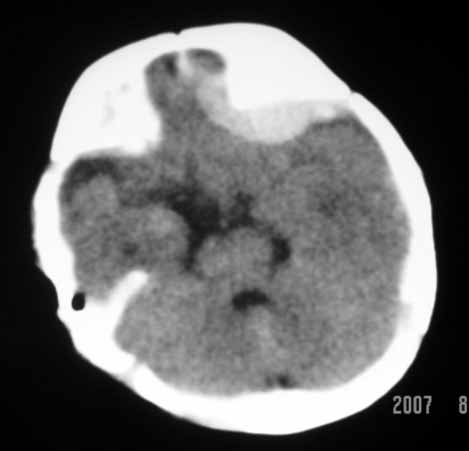

标题: PED0294: 2月婴儿.VitK缺乏症颅内出血.. [打印本页]

标题: PED0294: 2月婴儿.VitK缺乏症颅内出血..

可见 硬膜下及硬膜外血肿,蛛网膜下腔出血

以下是引用jiangjing在2007-8-2 15:07:00的发言:[br]可见 硬膜下及硬膜外血肿,蛛网膜下腔出血

vk缺乏症ct表现有脑实质内出血,珠网膜下腔,硬膜下出血,硬膜外出血,脑实质内出血少见。本病出血要点出血量大,多部位出血,脑室质出血呈团快状。